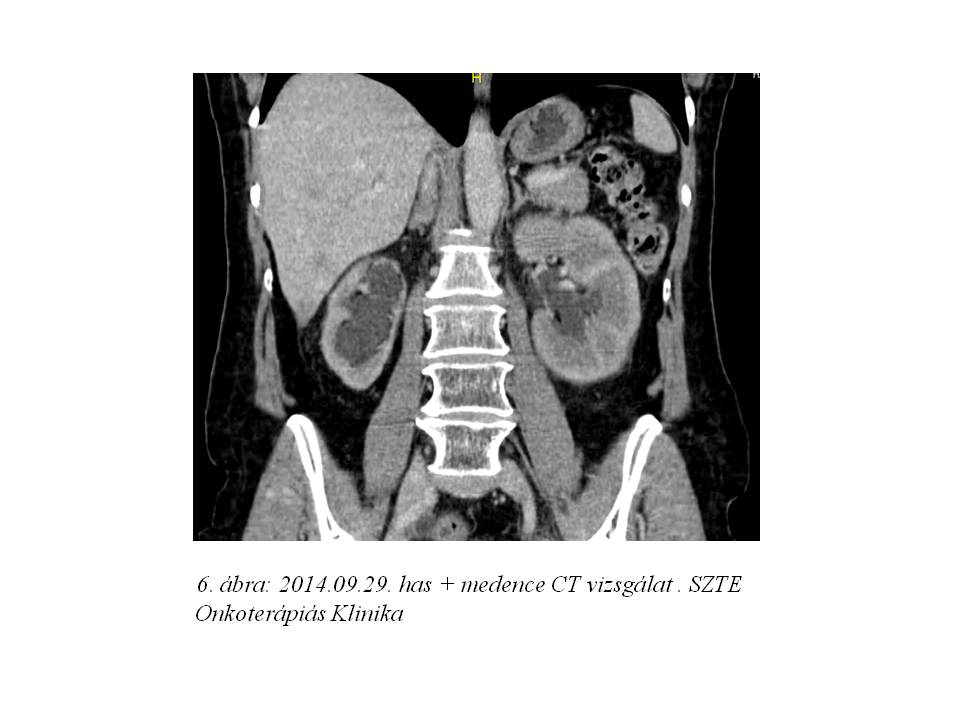

Folyamatosan emelkedő vesefunkciós paraméterek miatt azonban a palliatív kezelést nem tudtuk megkezdeni, nephrostoma beültetésére került sor. 2014. szeptemberben elvégzett friss has + medence CT mind a hepatikus metasztázisok, mind a vesepangás és a kismedencei recidíva rapid progresszióját igazolta (5. ábra, 6. ábra, 7. ábra). Mivel a vesefunkciós értékei későbbiekben sem engedték kemoterápiás kezelés indítását, szupportív terápia indult.